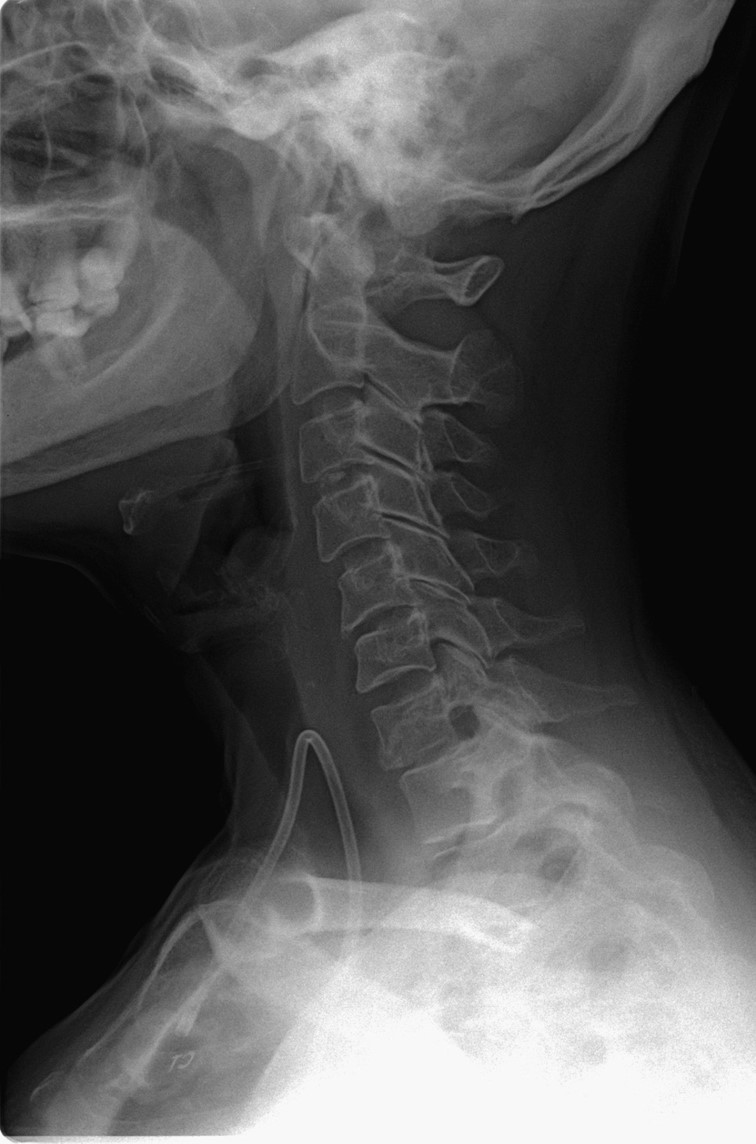

• C7 metastatik karsinoma

Ameliyat Öncesi